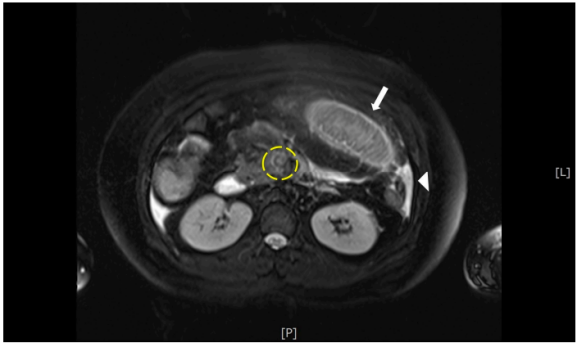

腹部超声检查显示10周大胎儿,母亲轻度腹水,没有急性胆囊炎或阑尾炎的超声迹象。进行磁共振成像(MRI),显示肠系膜上静脉(SMV)内T2高信号充盈缺损,小肠壁增厚和腹水(图1)。

图1. MRI显示肠系膜上静脉(黄色圆圈)内有高信号充盈缺损。还有小肠袢壁增厚(箭头所示)和少量腹水(箭头所示)